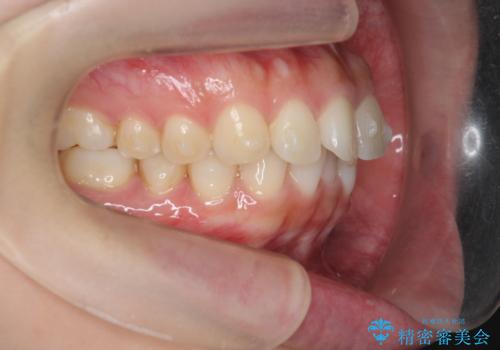

マウスピース 狭窄歯列の改善

- 噛み合わせが深い、笑った時の歯並びの改善を求めて来院されました。

マウスピース型の矯正装置インビザラインを用いた治療を計画します。

狭くなってしまった歯並びを放物線状に並べることで噛み合わせの安定・見た目の改善・ガタつきの改善を達成することができました。